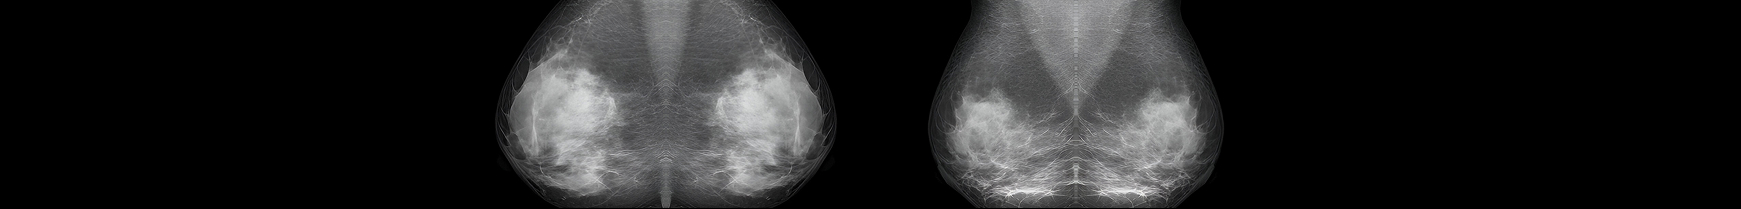

AI-Powered Breast Cancer Screening and Image Classification for Radiology